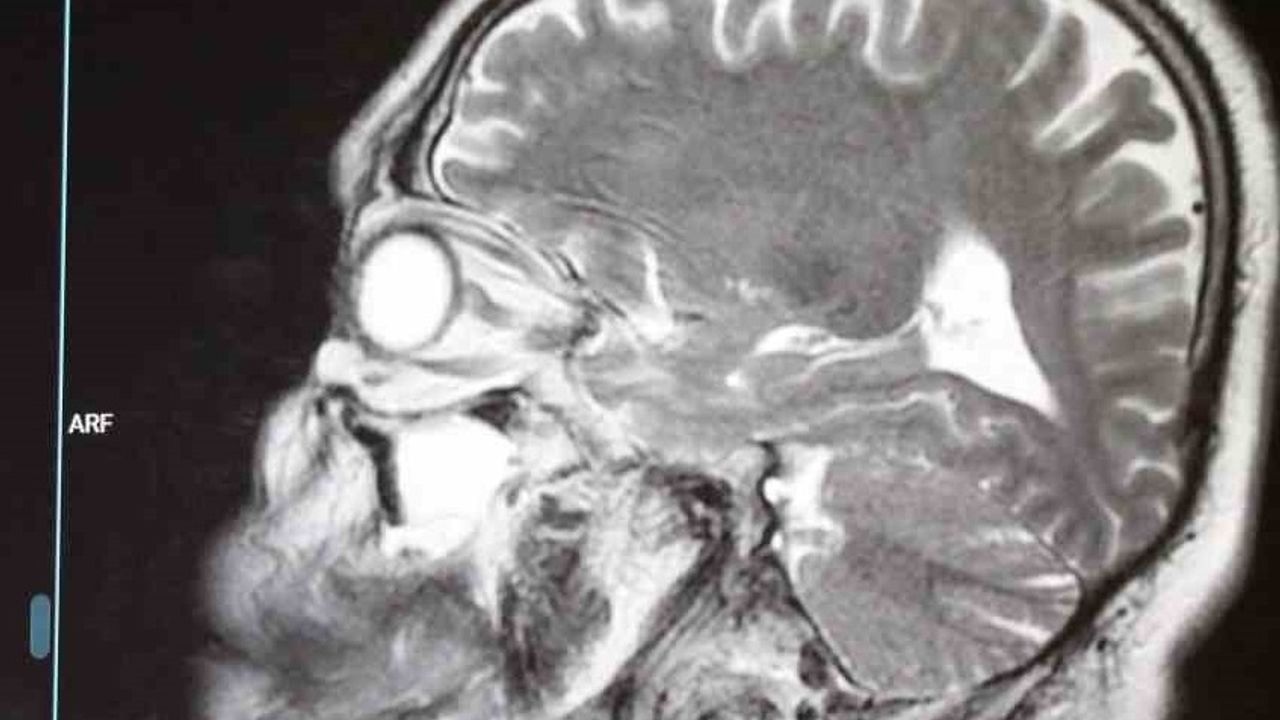

Beyin tümörleri hakkında değerlendirmelerde bulunan Prof. Dr. Fatih Serhat Erol, "Beyin tümörlerinin, beyin hücrelerinin kontrolsüz şekilde çoğalarak kitle oluşturması ve beyin dokusuna baskı yapmasıyla ortaya çıkıyor. Beyin tümörleri her yaşta görülebiliyor. Bazı tümör tiplerinin kadınlarda, bazılarının ise erkeklerde daha sık görülüyor. Bilimsel verilere göre 120’ye yakın beyin tümörü tipi bulunuyor. Beyin tümörlerinin, beyin hücrelerinden kaynaklanan birincil tümörler ve diğer organlardaki kanserlerin beyne yayılmasıyla oluşan metastatik tümörler olarak iki ana grupta incelenir. Tümörlerin oluşumunda genetik yapı, kafa travmaları, kimyasal maddelere veya radyasyona maruz kalma gibi etkenlerin rol oynayabilir. Ayrıca vücudunuzun bazı bölgelerindeki hücrelerin çok hızlı çoğalmasına neden olan nadir bir genetik hastalık gibi ve bazı sendromik hastalıkların da tümör oluşumuna zemin hazırlayabiliyor. Belirtiler arasında inatçı ve sürekli baş ağrılarının öne çıkıyor. Özellikle geceleri ve sabaha karşı artan baş ağrıları ve nöbet geçirmek önemli bir uyarıdır. Baş dönmesi, bulantı, kusma, denge kaybı, kol ve bacaklarda güçsüzlük, işitmede, koku almada ve görmede şikayetlerin de görülebiliyor. Hipofiz bezi tümörlerinde ise ellerde ve ayaklarda büyüme, tüylenmede artış ve adet düzensizlikleri gibi hormon kaynaklı belirtilerin ortaya çıkabilir. Tanı sürecinde detaylı bir öykü, fizik muayene ve görüntüleme yöntemlerinin büyük önem taşıyor. Özellikle ilaçlı beyin MR’ının tanıda altın standart oluyor. Beyin tümörlerinin büyük bölümünün cerrahi yöntemlerle tedavi ediliyor. Gerekli durumlarda biyopsi ile başlayıp, kemoterapi, radyoterapi veya radyo cerrahi gibi ek tedavilerin uygulanabilir. Bazı hastalarda ise yalnızca düzenli takiplerin yeterli olabilir" dedi.